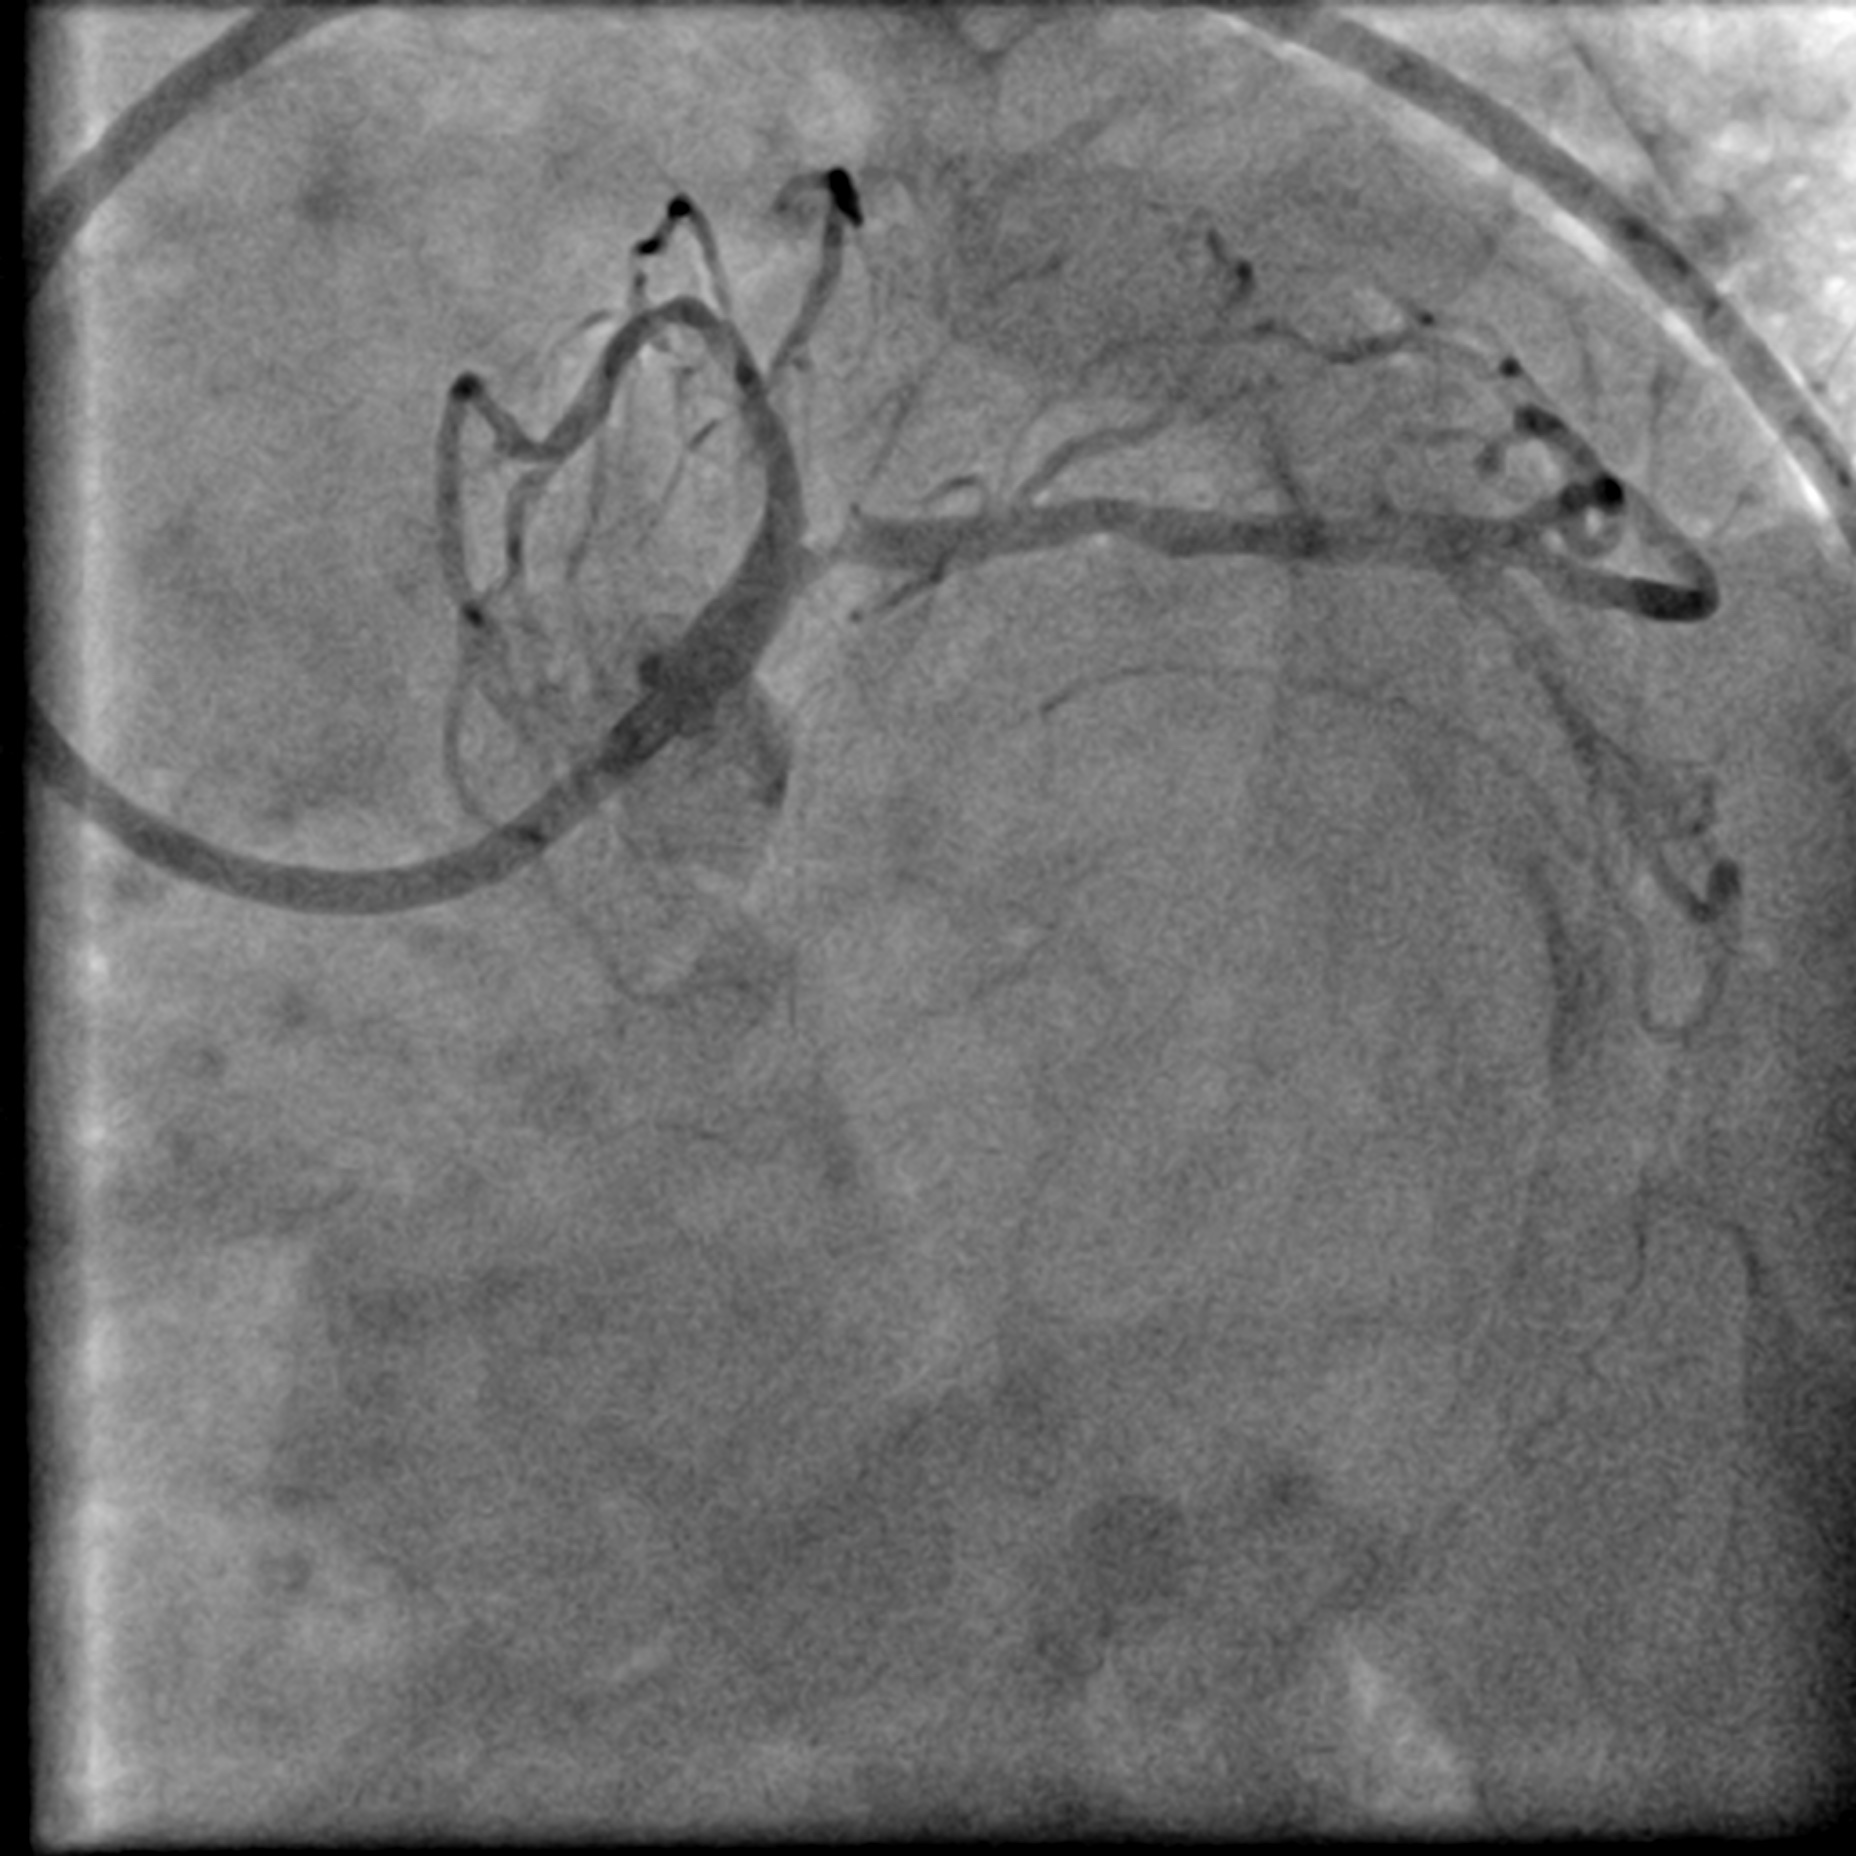

Coronary angiogram showed a Left Main Stem (LMS) bifurcation lesion (Medina 0,1,1) with visible calcification in the proximal left anterior descending artery (LAD). IVUS confirmed severe calcification in the proximal LAD and a calcified nodule causing significant occlusion at the left circumflex artery (LCx) ostium. The right coronary artery (RCA) was spared. Due to severe calcification, a calcium debulking device was required, and the decision was made to proceed with Orbital Atherectomy (OAS).

After positioning the ViperWire in the distal LAD, the OAS was delivered, and calcium debulking at low speed was performed safely. Afterward, the LAD was pre-dilated with a 2.5 mm scoring balloon and a 3.5 mm cutting balloon, while the LCx was pre-dilated with a 3.0 mm cutting balloon. A repeat angiogram revealed an Ellis 3 perforation in the proximal LAD, accompanied by a drop in the patient's blood pressure. Expeditiously, a 3.0 mm balloon was inflated at the perforation site, and its location was confirmed with an angiogram, which indicated immediate reduction of the perforation. A pigtail catheter was inserted simultaneously under echocardiographic guidance, and autologous blood transfusion was initiated. The perforation was covered with a 2.5 mm x 20 mm covered stent and post-dilated with a 3.0 mm NC balloon. This reduced the leak, but significant flow persisted. IVUS showed a gap between the stent strut and vessel wall near the LAD carina, allowing for persistent leakage. The covered stent was further post-dilated with a 3.5 mm NC balloon and a hugging balloon technique using two 2.5 mm balloons. These measures failed, as the maximal expansion of the 2.5 mm covered stent is limited to 3.0 mm. A Kissing Balloon Technique (KBT) was attempted at the bifurcation, but it proved futile. Finally, a second 3.5 mm covered stent was placed proximally, which successfully sealed the perforation, leaving only a trivial leak. The hemoperricardium resolved after 24 hours.